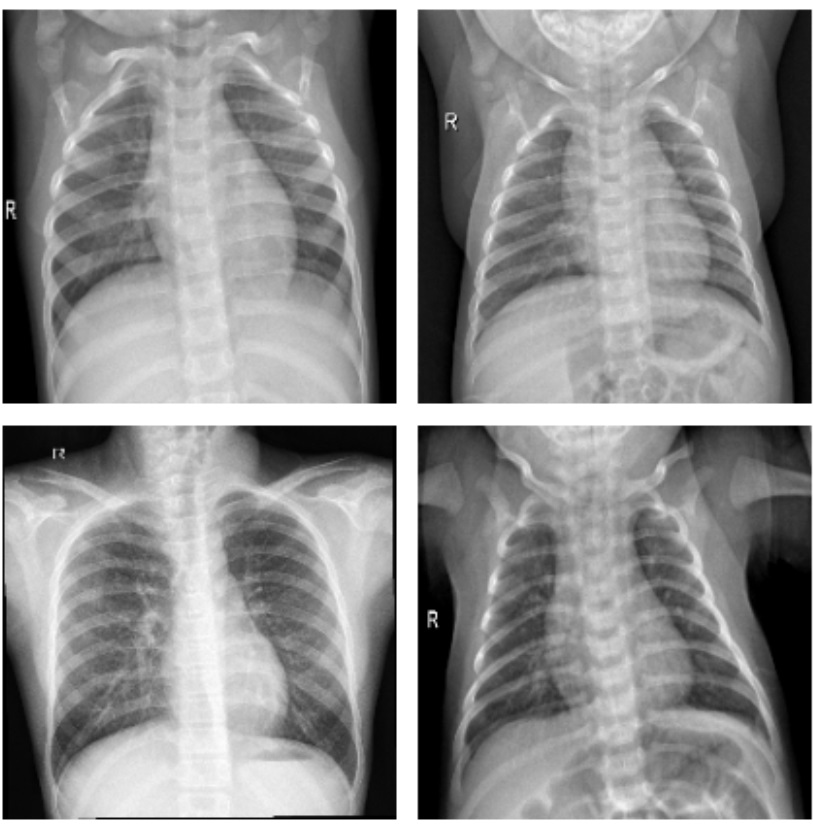

肺炎是全球范围内致死率较高的疾病之一,尤其是在老年人、免疫系统较弱的患者群体中,更容易引发严重并发症。传统上,肺炎的诊断依赖于医生的临床经验以及影像学检查,尤其是X光片,它在肺炎的早期筛查和诊断中扮演了至关重要的角色。然而,X光片的读取不仅需要专业的放射科医生,而且受到经验和疲劳等因素的影响,导致诊断结果的准确性存在一定的偏差。近年来,人工智能(AI)技术,尤其是深度学习在医学影像领域取得了显著进展。通过深度学习模型,计算机能够高效地从大量影像数据中学习到复杂的模式,并实现对疾病的自动识别和分类,极大地提高了诊断的速度和准确性。迁移学习作为深度学习的一种重要方法,能够通过在已有的、大规模的医学图像数据上预训练模型,并迁移到肺炎X光片的分类任务上,减少对大量标注数据的需求,这对资源有限、标注困难的医学领域尤为重要。

基于迁移学习的肺炎X光片诊断分类研究,不仅可以缓解医生在实际工作中因繁重工作负担导致的诊断错误问题,还能够通过高效、准确的自动化诊断方法,在早期筛查中提供帮助,尤其是在偏远地区或医疗资源匮乏的环境中,为患者提供及时的诊疗建议,极大地促进了医疗资源的合理分配。此外,该研究的成功实现还可以为其他疾病的X光片图像诊断提供借鉴,推动人工智能技术在医学领域的广泛应用。下面开始代码实战。